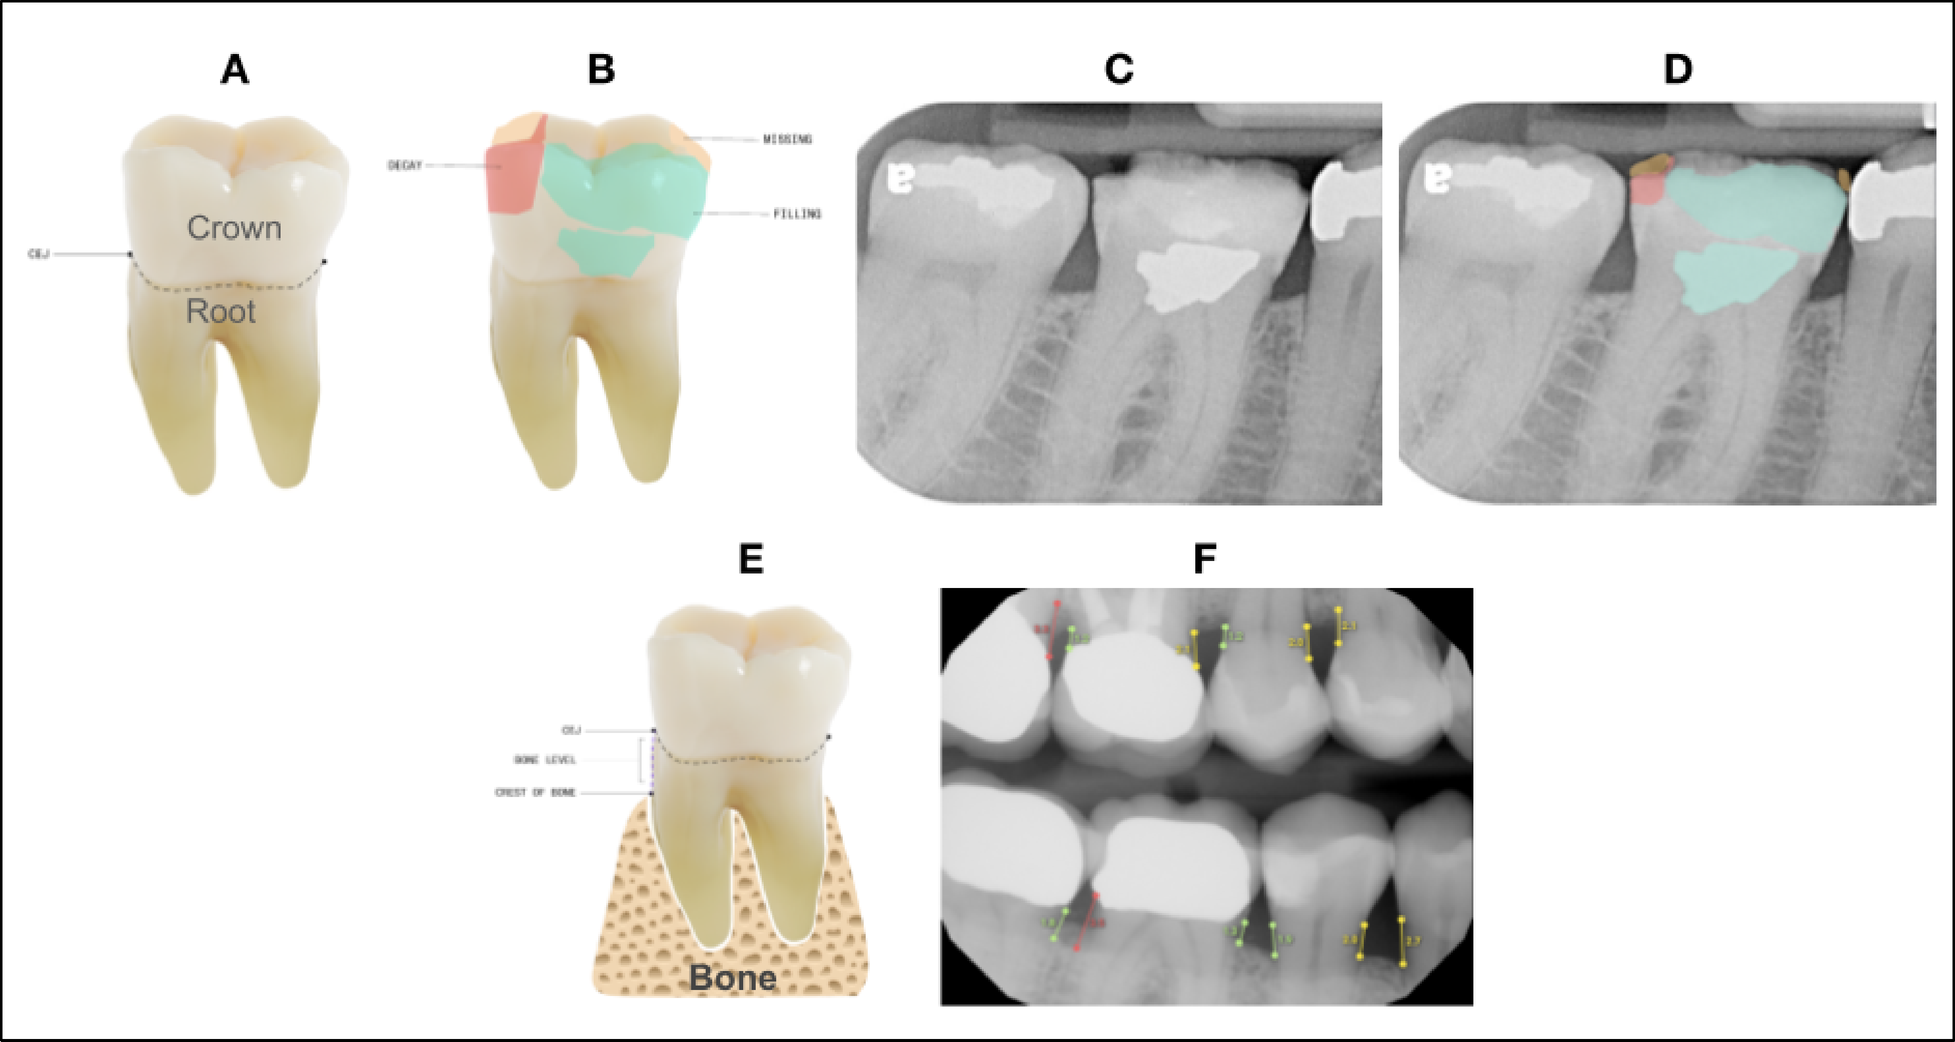

Top ROW: The teeth images (A) and (B) are used to illustrate 2-dimensional segmentations similar to the radiographs (C) and (D). From the top left, in image (A) illustrates the location of the CEJ on the tooth. The portion of the tooth identified as above or coronal to the dotted line is defined as the coronal portion of the tooth, and the area of the tooth below or apical to the CEJ is considered the root portion of the tooth. Image (B) depicts in 2 dimensions how the tooth is segmented to calculate DMFP by identifying the coronal portion of the tooth that is decayed (red), missing (orange), and filled (green). Image (C) shows a standard periapical radiograph without AI generated predictions. Image (D) shows the AI-analyzed image illustrating the decayed, missing and filled segmentations on this radiograph. The DMFP calculation for tooth number 30 is 0.71. Bottom Row: Image (E) illustrates the anatomical landmarks that are used to measure the interproximal alveolar bone level: CEJ and crest of bone. The distance between these two points is the reported bone level (BL). This measurement is analyzed on the mesial and distal of each tooth on the radiograph and can be seen on the bone level image (F).